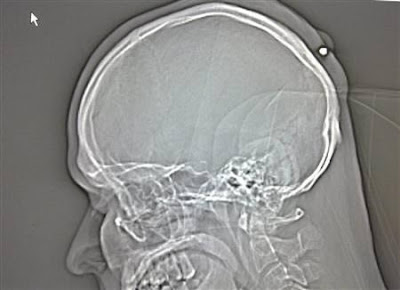

Seorang pria yang hidup di Jerman hidup dengan normal dan baik-baik saja selama lima tahun tanpa menyadari ia telah ditembak di kepala. Peluru kaliber 0,22 ditemukan ketika orang itu pergi ke dokter untuk memiliki apa yang ia pikir merupakan kista .

Yang dia ingat adalah bahwa ia telah menerima pukulan ke kepala sekitar tengah malam di sebuah pesta Tahun Baru “di tahun 2004, atau 2005″ tapi sudah lupa tentang hal itu karena ia “sangat mabuk.”